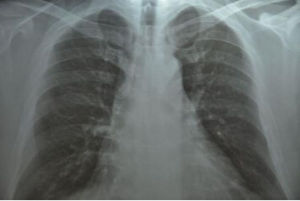

常引起本症狀的疾病有慢性支氣管炎、支氣管擴張、風心病、先心病、塵肺、癌性淋巴管炎等呼吸和心律增快、肺部羅音、肺動脈瓣第二心音亢進。胸片呈現肺部斑片狀

肺紋理增粗檢查

(1)支氣管性肺紋理增多:表現為肺紋理粗細不勻,其中常夾雜變形紋理和小蜂窩影,常見於慢性支氣管炎、支氣管擴張等。(2)血管性肺紋理增多:肺紋理粗大,從肺門向肺內保持血管走行的特性,常伴有心臟增大的表現,主要見於風心病、先心病等。(3)淋巴性肺紋理增多:肺紋理在兩肺內呈纖細的網狀,常見於塵肺、癌性淋巴管炎等。(4)吸菸性肺紋理增多:顯示雙肺紋理增多,但走行正常,主要是由於長期吸菸引起的炭末沉著症所致。(5)生理性肺紋理增多:主要見於老年人和肥胖者。前者是由於老年人肺間質相對較豐富,從而在X線胸片上顯示肺紋理增多;後者是由於受檢者體質肥胖,皮下脂肪增多,導致X線吸收增加,從而引起胸片上肺紋理增多的假象。鑑別診斷